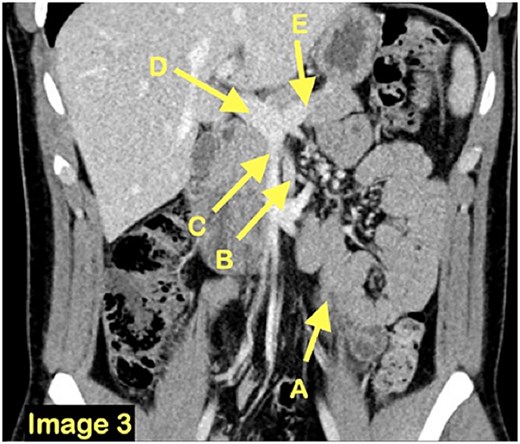

A coronal CT scan view demonstrating once again the clustered small bowel loops (A) and the surrounding vasculature inferior mesenteric vein (B), superior mesenteric vein (C), portal vein (D) and splenic vein (E).